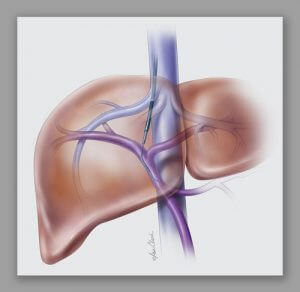

Transjugular intrahepatic portosystemic shunt (TIPS) is a procedure that creates new connections between two blood vessels in your liver.

The doctor inserts a catheter through your skin and into your jugular vein. Guided by x-ray imaging, the doctor guides the catheter into the hepatic vein in your liver. The doctor then creates a pathway through the liver for a stent that will connect the hepatic and portal systems. This new pathway helps to lower pressure in the portal system.